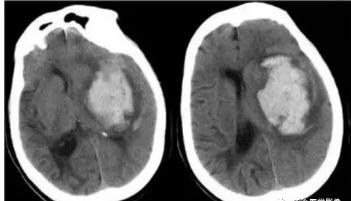

一、内囊出血:

是最常见的出血部位。其典型临床表现为对侧"三偏"(偏瘫、偏身感觉障碍、偏盲)。内囊出血范围较大,神经损害症状较重。但若出血偏于内囊外侧,主要损害外囊部位,则临床症状多较轻些,多无意识障碍,偏瘫也轻,预后较好。

左侧基底节区较大范围高密度影,边界清晰,周围可见低密度水肿,左侧侧脑脑室消失闭塞,中线结构右移。